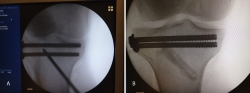

La artroscopia comenzó a utilizarse para asistir/controlar la reducción de las fracturas de meseta tibial, ya que la rodilla es la articulación en la que comenzó la artroscopia (Figura 1).

A raíz del artículo de Caspari(11), comenzamos a utilizar la artroscopia en nuestro medio en las fracturas de meseta tibial Schatzker de tipo II, en las que realizábamos la elevación del fragmento hundido mediante el uso de impactores desde la zona diafisometafisaria de la tibia, relleno del defecto con cemento biocompatible y fijación con tornillos canulados con arandela. Publicamos nuestra experiencia en los Cuadernos de Artroscopia en 1998(12)(Figuras 2 y 3).

Figura 1. Visión del cirujano de la reducción articular en una fractura de meseta tibial.

Figura 2. Técnica quirúrgica en fracturas de meseta tibial asistidas por artroscopia: elevación del fragmento hundido mediante impactor.

Figura 3. Técnica quirúrgica en fracturas de meseta tibial asistidas por artroscopia: relleno con cemento biocompatible y fijación con tornillos canulados de esponjosa.